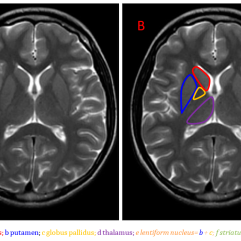

An Introduction to Huntington’s Disease

Huntington’s Disease (HD) is a rare, incurable, inherited and ultimately fatal neurodegenerative disorder characterised by chorea, ataxia, dysphagia, cognitive and behavioural changes. Current therapies offer only symptomatic relief, and many are associated with significant side effects, though pridopidine, a sigma-1-receptor (S1R) agonist has shown potential for both symptomatic treatment and disease modifying effects in HD. Advances in our understanding of the pathogenesis of HD have highlighted the importance of DNA repair genes, and novel approaches, such as the antisense therapy tominersen and the oral agent branaplam, are targeting the mutant huntingtin (mHTT) protein and the HTT gene. However, no disease-modifying therapy is yet approved for HD.